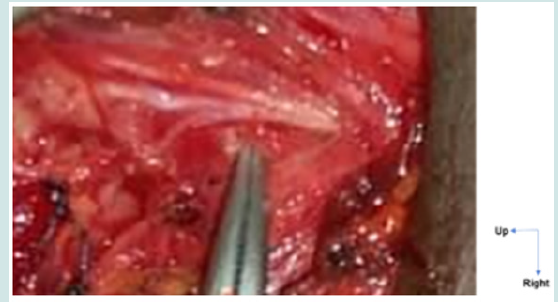

Figure 1: ILN with its esophageal branch.